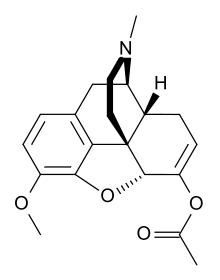

Codeine-dionine family

Structures

| Codeine-dionine family | ||||

|---|---|---|---|---|

6-Monoacetylcodeine 6-Monoacetylcodeine |

Benzylmorphine Benzylmorphine |

Codeine methylbromide Codeine methylbromide |

Desocodeine Desocodeine |

Dimethylmorphine Dimethylmorphine(6-O-Methylcodeine) |

Ethyldihydromorphine Ethyldihydromorphine |

Methyldihydromorphine Methyldihydromorphine(dihydroheterocodeine) |

Ethylmorphine Ethylmorphine |

Heterocodeine Heterocodeine |

Isocodeine Isocodeine |

Pholcodine Pholcodine |

Myrophine Myrophine |

Transisocodeine Transisocodeine | ||